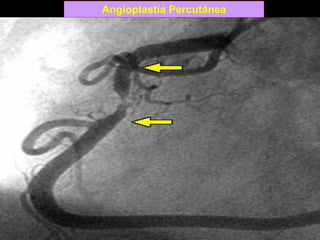

Angioplastía Percutánea